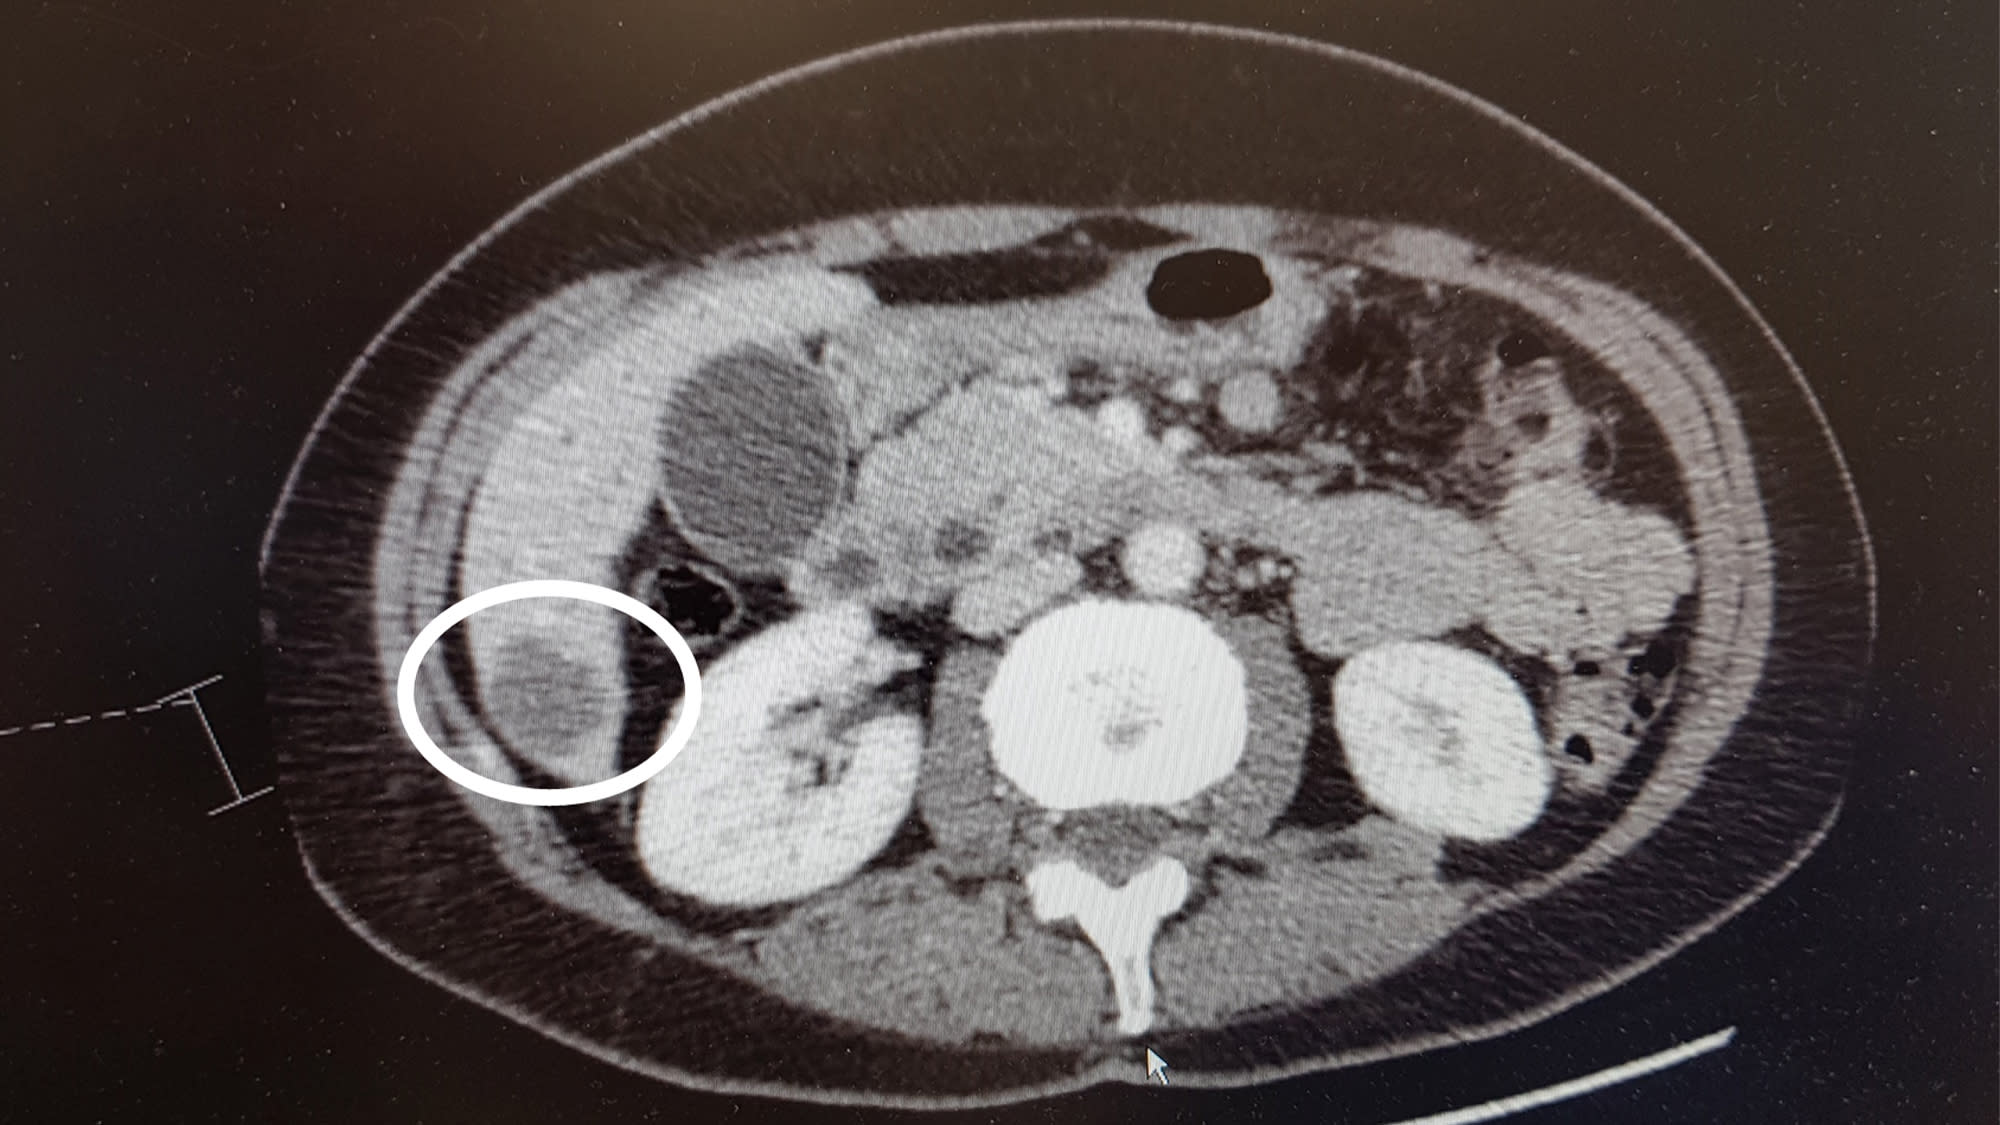

Cancerindikatorn har minskat från 186 till 18! Huvudtumören i bukspottkörteln går knappt att urskilja. Samma gäller för dottertumörerna i gallgången och tolvfingertarmen. De två metastaserna i levern har minskat rejält i storlek och flera av de tio metastaserna i lungorna harminskat i storlek och i vissa fall, försvunnit.

Cancerindikatorstestet har sjunkit från 18 till 15! Av de sammanlagt 14 metastaserna och en huvudtumör som jag diagnostiserades med i maj 2020 har jag bara en metastas kvar i levern och en i lungorna.

Vi har ett resultat! Cancerindikatorn har sjunkit ytterligare två steg och referensröntgen visar att metastasen i levern endast ser ut som ett ärr nu. Den är i stort sett helt borta. Har fortfarande några små prickar i lungorna, men de är pyttesmå.